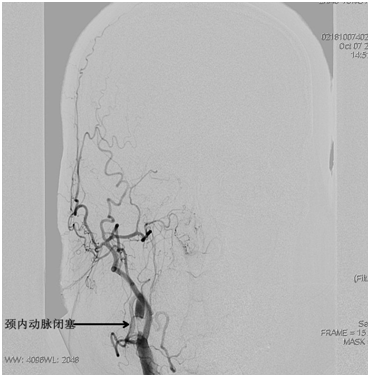

韩金涛副主任医师凭借丰富的临床经验,判断本次急性脑梗塞的根源在于右侧颈内动脉起始段急性闭塞(图1)。在从家中赶来支援的贾子昌主治医师和隋玉洁主管护师的熟练配合下,沉着而迅速进行了闭塞的右侧颈内动脉急诊成形术。历时不到1小时,患者的右侧颈内动脉得以恢复通畅血流(图2)。术后即刻,尚躺在手术床上的患者神志即恢复清醒,而且左侧肢体肌力恢复至较满意水平(图3-4)。

图1